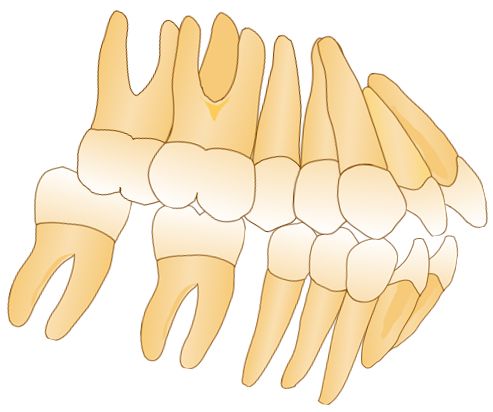

47牙前移的矫治设计:每步移动0.2mm,6°后倾分散施加在每步矫治中,与对合设计咬合重接触。

移动分步设计:47牙与45牙先相互移动,47牙与45牙移动至预计移动量一半时,48牙与44牙再移动,47牙与48牙间始终留有间隙。